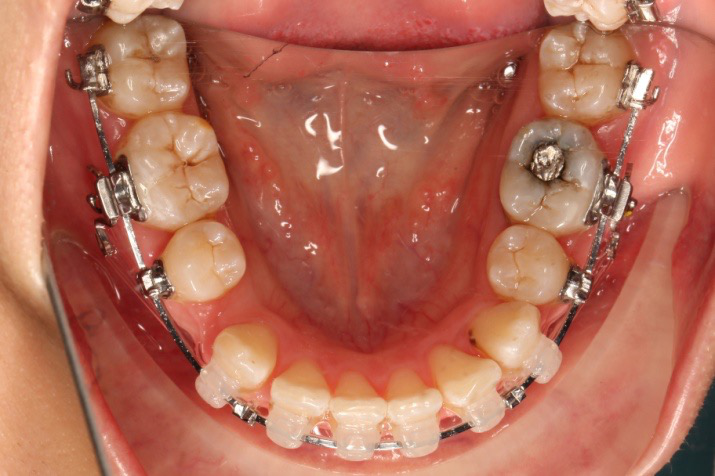

1.第0个月:2016.10.31 ◆ 初戴,0.013cu-niti

2.第2.5个月:2017.1.13 ◆ 上颌加TPA,植入1312-08种植钉,上下0.16cu-niti

3.第3.5个月:2017.02.16 ◆ 上下0.014*25 cu-niti,50g 尖牙远中

2016.10.31  初戴,0.013cu-niti2017.1.13  上颌加TPA,U56间斜形植入韩国庆北1312-08种植钉,上下0.16cu-niti

2017.02.16  上下0.014*25 cu-niti,50g 拉尖牙远中